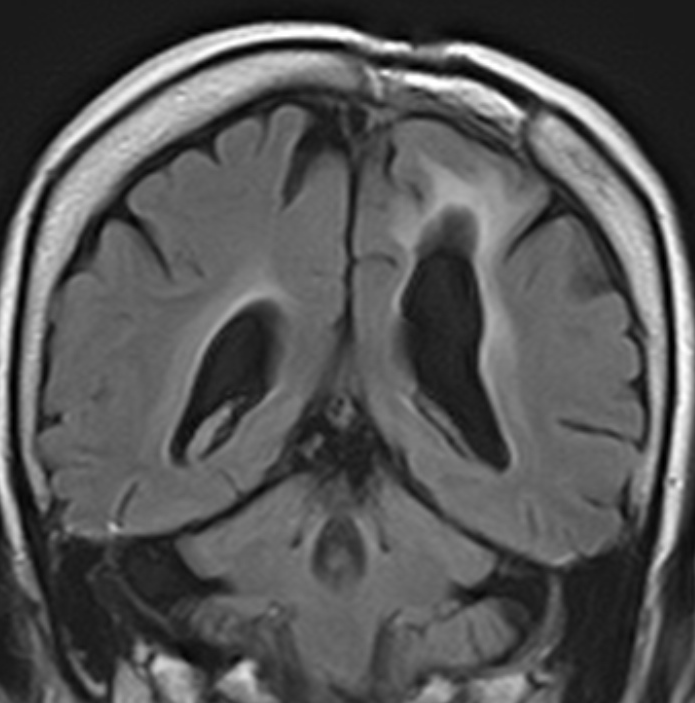

12歳時,私のところへ来た時のガドリニウム増強像です。開頭手術で扁桃体を含めて全摘出してから発作は止まり,術後3年で抗てんかん薬は中断できています。